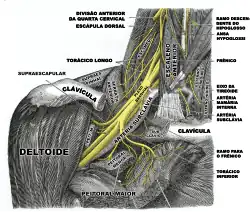

O ombro é o segmento mais proximal do membro superior, que se sobrepõe a parte do tronco (tórax e dorso), bem como porção ínfero-lateral do pescoço. Abrange as regiões deltoidea (na qual está o músculo deltoide), escapular (que contém a escápula) e peitoral (em que se encontra o músculo peitoral maior). Abriga também o cíngulo do membro superior, responsável por fixar o membro superior ao resto do corpo.[2]

Primeiramente, faz parte desse conjunto de ossos o chamado cíngulo do membro superior, responsável por unir o membro ao esqueleto axial. No caso do membro superior, o cíngulo é formado pela clavícula e pela escápula.[2]

A clavícula e a escápula integram o cíngulo do membro superior, responsável por fixá-lo ao tronco.[2] Tal fixação envolve algumas articulações. Primeiramente, a face esternal da clavícula se articula com o esterno, precisamente com a incisura clavicular do manúbrio do esterno. A junta formada, que recebe o nome de articulação esternoclavicular, tem um encaixe similar ao estabelecido entre uma sela e o dorso de um cavalo, logo é classificada como articulação sinovial selar. Ela possibilita que a clavícula se eleve e retorne à sua posição inicial, conforme o ombro se eleva ou se deprime, respectivamente; bem como se retraia ou se protraia, ao longo da retrusão ou protrasão da escápula, respectivamente.[10][11]

Na sequência, a outra face da clavícula, denominada extremidade acromial da clavícula, estabelece articulação com o acrômio da escápula. Trata-se de uma articulação sinovial plana, responsável pelo deslizamento entre clavícula e escápula durante os movimentos da escápula. A clavícula, com sua disposição, funciona como uma escora, de modo a afastar o membro superior do tronco e, de tal maneira, dá-lo máxima liberdade de movimento.[2]

Embora a abundância de articulações sinoviais dê a base para a imensa mobilidade do membro superior, é a musculatura que, ativamente, movimenta seu esqueleto.[19] Há, portanto, variados músculos estriados esqueléticos no membro superior. Entre aqueles que movimentam o ombro, podemos citar os músculos do manguito rotador. Já no braço, encontramos, por exemplo, o bíceps braquial e o tríceps braquial. No antebraço, há, entre outros, o supinador e os pronadores redondo e quadrado. Por fim, na mão, existe o ápice da complexidade anatômica do membro superior, com uma variedade imensa de musculatura, além das já vistas riquezas de ossos e articulações sinoviais na região.[3]